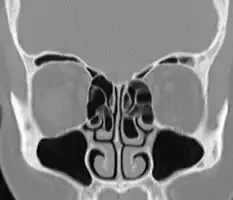

- Bilateral concha bullosa, larger on the left